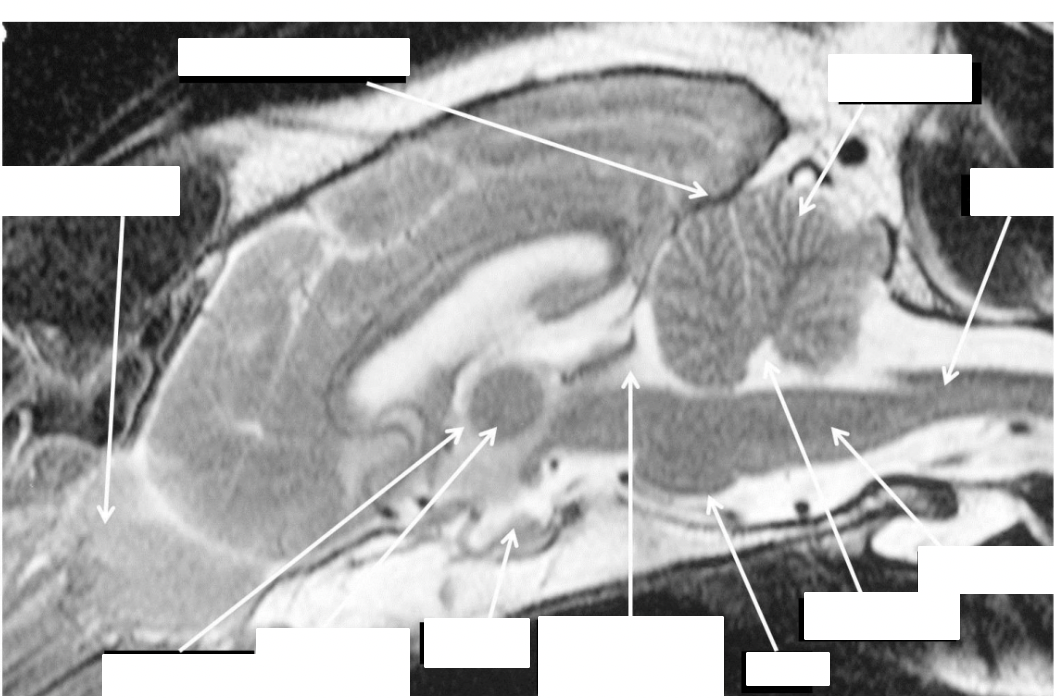

what are the structures shown

blue: interthalamic adhesion

red: brain stem

silver: spinal cord

identifty the interthalamic adhesion, brain stem, spinal cord